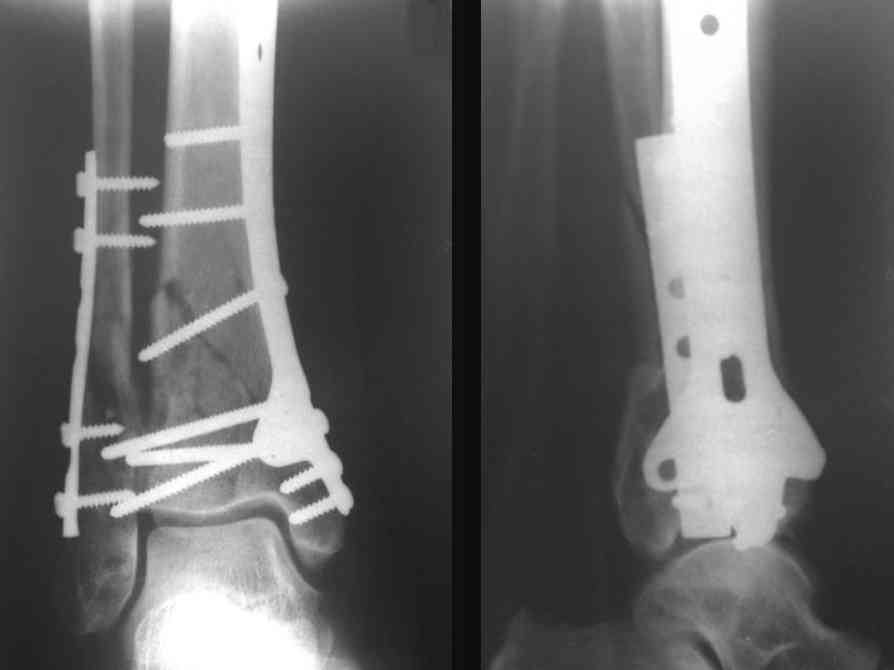

На рентгенограммах типичный перелом пилона по типу С-3. есть опыт до 100 открытых опреаций у нас в клинике. 20 примерно в год. Принцип один -все внутрисуставные переломы нуждаются в открытой репозиции и внутренней стабильной фиксации. При поступлении КТ не надо, так как получается только нагромождение костей. Истинной картины нет. Главное восстановить длину малоберцовой кости - это ключ к успеху. При поступлении меньше всего надо думать о сосудистых расстройствах, т.к. сама операция и репозиция даже сначала частичная даёт улучшение сосудитых нарушений. Причём очень быстро. Операция в 2этапа. При поступлении доступ позади наружной лодыжки, причём обязательно. После этого репозиция малоберцовой кости и фиксация пластиной 1/3 трубки под винт 3,5. Дренаж и любой аппарат наружной фиксации. Затем после спадения отёка на 5-7-10 день аппрат снимается и дугообразный разрез спереди от медиальной лодыжки 10-12 см. Главной чтобы расстояние между 1 и вторым разрезом было не меньше 7-8 см. Тогда не будет некрозов лоскутов. Таранная кость используется как матрица на неё укладываются отломки и фиксируются пицами. Ренг-контроль. Отломки лежат все отдельно, но ничего не высыпется. При переломах С-3 всегда нужна костная пластика (из крыла). Фиксация пластиной лист клевера простой или LCP. Гипс не нужен. Дренаж до 48 часов. Операция длится 3-4 часа обязательно без жгута. Посылаю примерно такой же случай.

Ещё есть одна проблема когда есть перелом малоберцовой кость, то всё ясно. А когда малоберцовая кость не повреждена, то сразу накладывается аппрат наружной фиксации при поступлении, чтобы как бы перерастянуть отломки и главное убрать вальгусное или варусное смещение, а потом на 5-7 день открыто большеберцовая кость восстанавливается и фиксируется пластиной. С уважением Дрягин

Кстати, при переломах переднего края по классификации АО В-3 при переломах пилона пластина укладывается по передней поверхности. Она достаточно тонкая и эластичная, не надо этого бояться. Посылаю три снимка.